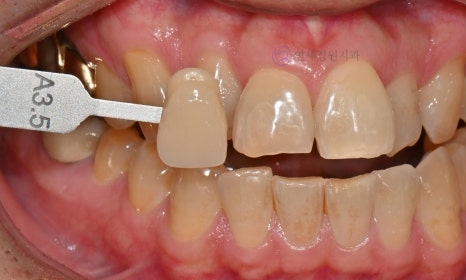

Before starting the teeth whitening process, the color of your teeth will be assessed. A shade guide will be used to record the tooth color; the shade guide is a specific indicator that expresses the degree of lightness or darkness of the teeth in stages. As the letters increase numerically, the color becomes darker. Tooth colors are classified into 16 stages, ranging from B1 to C4 (B1-A1-B2-D2-A2-C1-C2-D4-A3-D3-B3-A3.5-B4-C3-A4-C4). The closer to B1, the brighter the natural tooth color, and the closer to C4, the darker the color.

Before and After

Before Shade: A3.5 / After Shade: A2